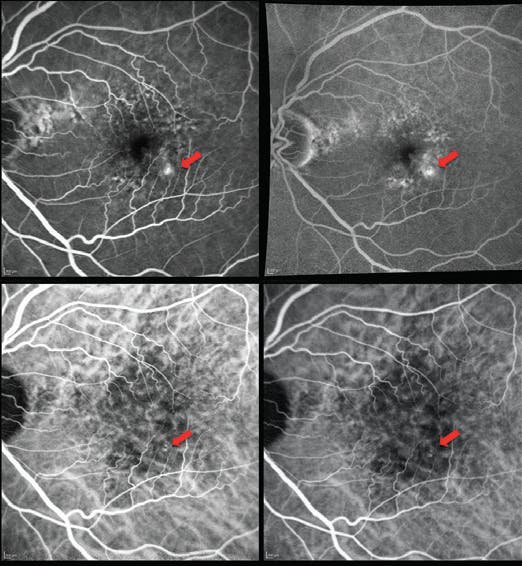

<p>Figure 3. FA and ICG angiography of the right eye showed a vertically diving retinal vessel with retina–retina anastomosis.</p>

Figure 3. FA and ICG angiography of the right eye showed a vertically diving retinal vessel with retina–retina anastomosis.